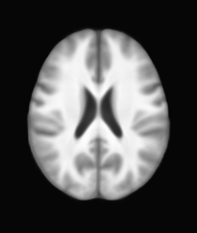

[Uncaptioned image] [Uncaptioned image] [Uncaptioned image] [Uncaptioned image]

(a) (b) (c) (d)

Figure 8: Example BRATS image with its decomposition result in atlas space. (a) Input image after pre-processing; (b) quasi-normal image L+M𝐿𝑀L+M; (c) non-brain image S𝑆S; (d) pathology image T𝑇T.

In addition to extracting the brain from pathological datasets, our method also allows for the estimation of a corresponding quasi-normal image in atlas space, although this is not the main goal of this paper. Fig.8 shows an example of the reconstructed quasi-normal image (L𝐿L) for an image of the BRATS dataset, as well as an estimation of the pathology (pathology image T𝑇T and non-brain image S𝑆S). Compared to the original image, the pathology shown in the quasi-normal image has been greatly reduced. Hence this image can be used for the registration with a normal image or a normal atlas. This has been shown to improve registration accuracy for the registration of pathological images [27]. Furthermore, an estimate of the pathology (here a tumor) is also obtained which may be useful for further analysis. Note that in this example image the total variation term captures more than just the tumor. This may be due to inconsistencies in the image appearance between the normal images (obtained from OASIS data) and the test dataset. As our goal is atlas alignment rather than quasi-normal image reconstruction or pathology segmentation, such a decomposition is acceptable, although we could improve this by tuning the parameters or applying regularization steps as in [27].